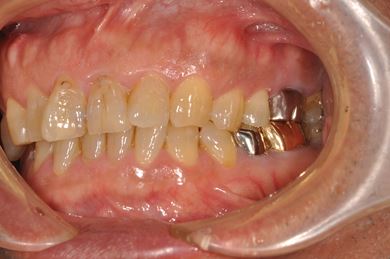

インプラント治療+セラミック治療

| 性別/年齢 | 男性 / 58歳 | ||||||||||||||||||||||||||||||||

| 主訴 | 部分入れ歯のバーが舌に当たるため、奥歯2本のインプラント治療を希望。 | ||||||||||||||||||||||||||||||||

| 治療方針 | 右下欠損部分をインプラント治療にて、機能的・審美的回復を行う。 | ||||||||||||||||||||||||||||||||

| 治療内容 | インプラント2本、メタルボンドセラミッククラウン8本、メタルボンドセラミック用土台6本 | ||||||||||||||||||||||||||||||||

| 総治療費 | 1,474,620円 | ||||||||||||||||||||||||||||||||

| 治療期間 | 1年6ヶ月 |